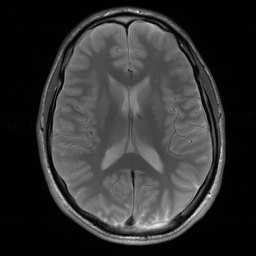

Magnetic Resonance Imaging (MRI) has excellent soft tissue contrast but is hindered by an inherently slow data acquisition process. Compressed sensing, which reconstructs sparse signals from incoherently sampled data, has been widely applied to accelerate MRI acquisitions. Compressed sensing MRI requires one or more model parameters to be tuned, which is usually done by hand, giving sub-optimal tuning in general. To address this issue, we build on previous work by the authors on the single-coil Variable Density Approximate Message Passing (VDAMP) algorithm, extending the framework to multiple receiver coils to propose the Parallel VDAMP (P-VDAMP) algorithm. For Bernoulli random variable density sampling, P-VDAMP obeys a "state evolution", where the intermediate per-iteration image estimate is distributed according to the ground truth corrupted by a zero-mean Gaussian vector with approximately known covariance. To our knowledge, P-VDAMP is the first algorithm for multi-coil MRI data that obeys a state evolution with accurately tracked parameters. We leverage state evolution to automatically tune sparse parameters on-the-fly with Stein's Unbiased Risk Estimate (SURE). P-VDAMP is evaluated on brain, knee and angiogram datasets and compared with four variants of the Fast Iterative Shrinkage-Thresholding algorithm (FISTA), including two tuning-free variants from the literature. The proposed method is found to have a similar reconstruction quality and time to convergence as FISTA with an optimally tuned sparse weighting and offers substantial robustness and reconstruction quality improvements over competing tuning-free methods.